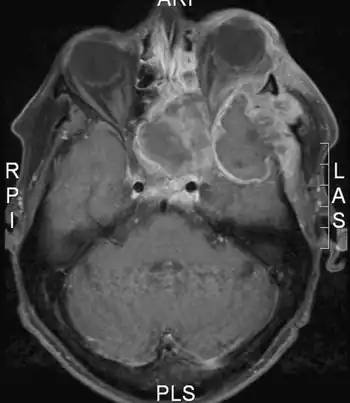

| Image shows huge plasmablastic lymphoma infiltrating the left orbit | |